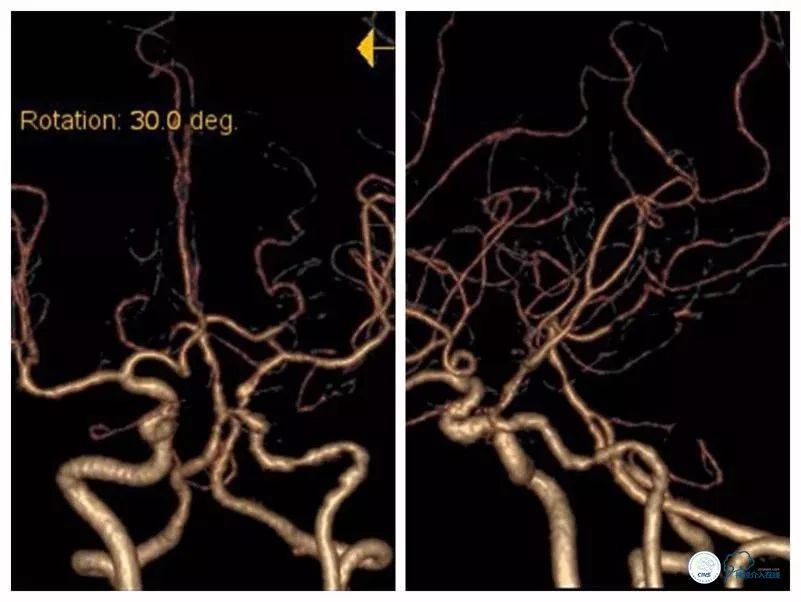

本例患者狭窄程度较硬,微导丝通过病变后但微导管无法跟进,由于首过病变的微导丝系200cm短导丝,遂只能采用分节剪短微管方法撤出微导丝(图17)。

图17

此外受限微导丝长度,也不能使用自膨支架。所幸,使用8F导引导管+6F Navien导管,系统支撑性较强,两枚Apollo支架均能到位,才得以顺利完成治疗。术后患者出现眼动脉栓塞症状,予以处理后病情缓解,目前电话随访患者眼部症状消失。